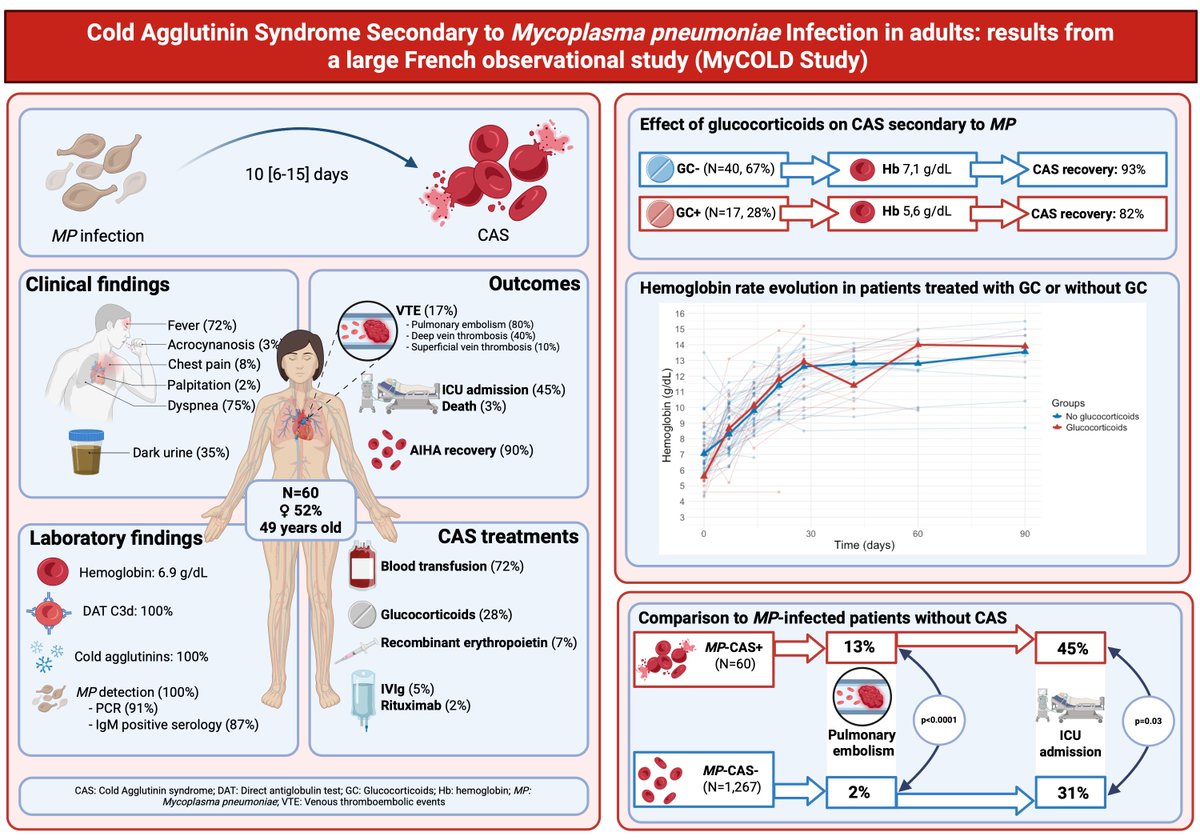

Bravo à Thibault Comont, MD et collaborateurs !